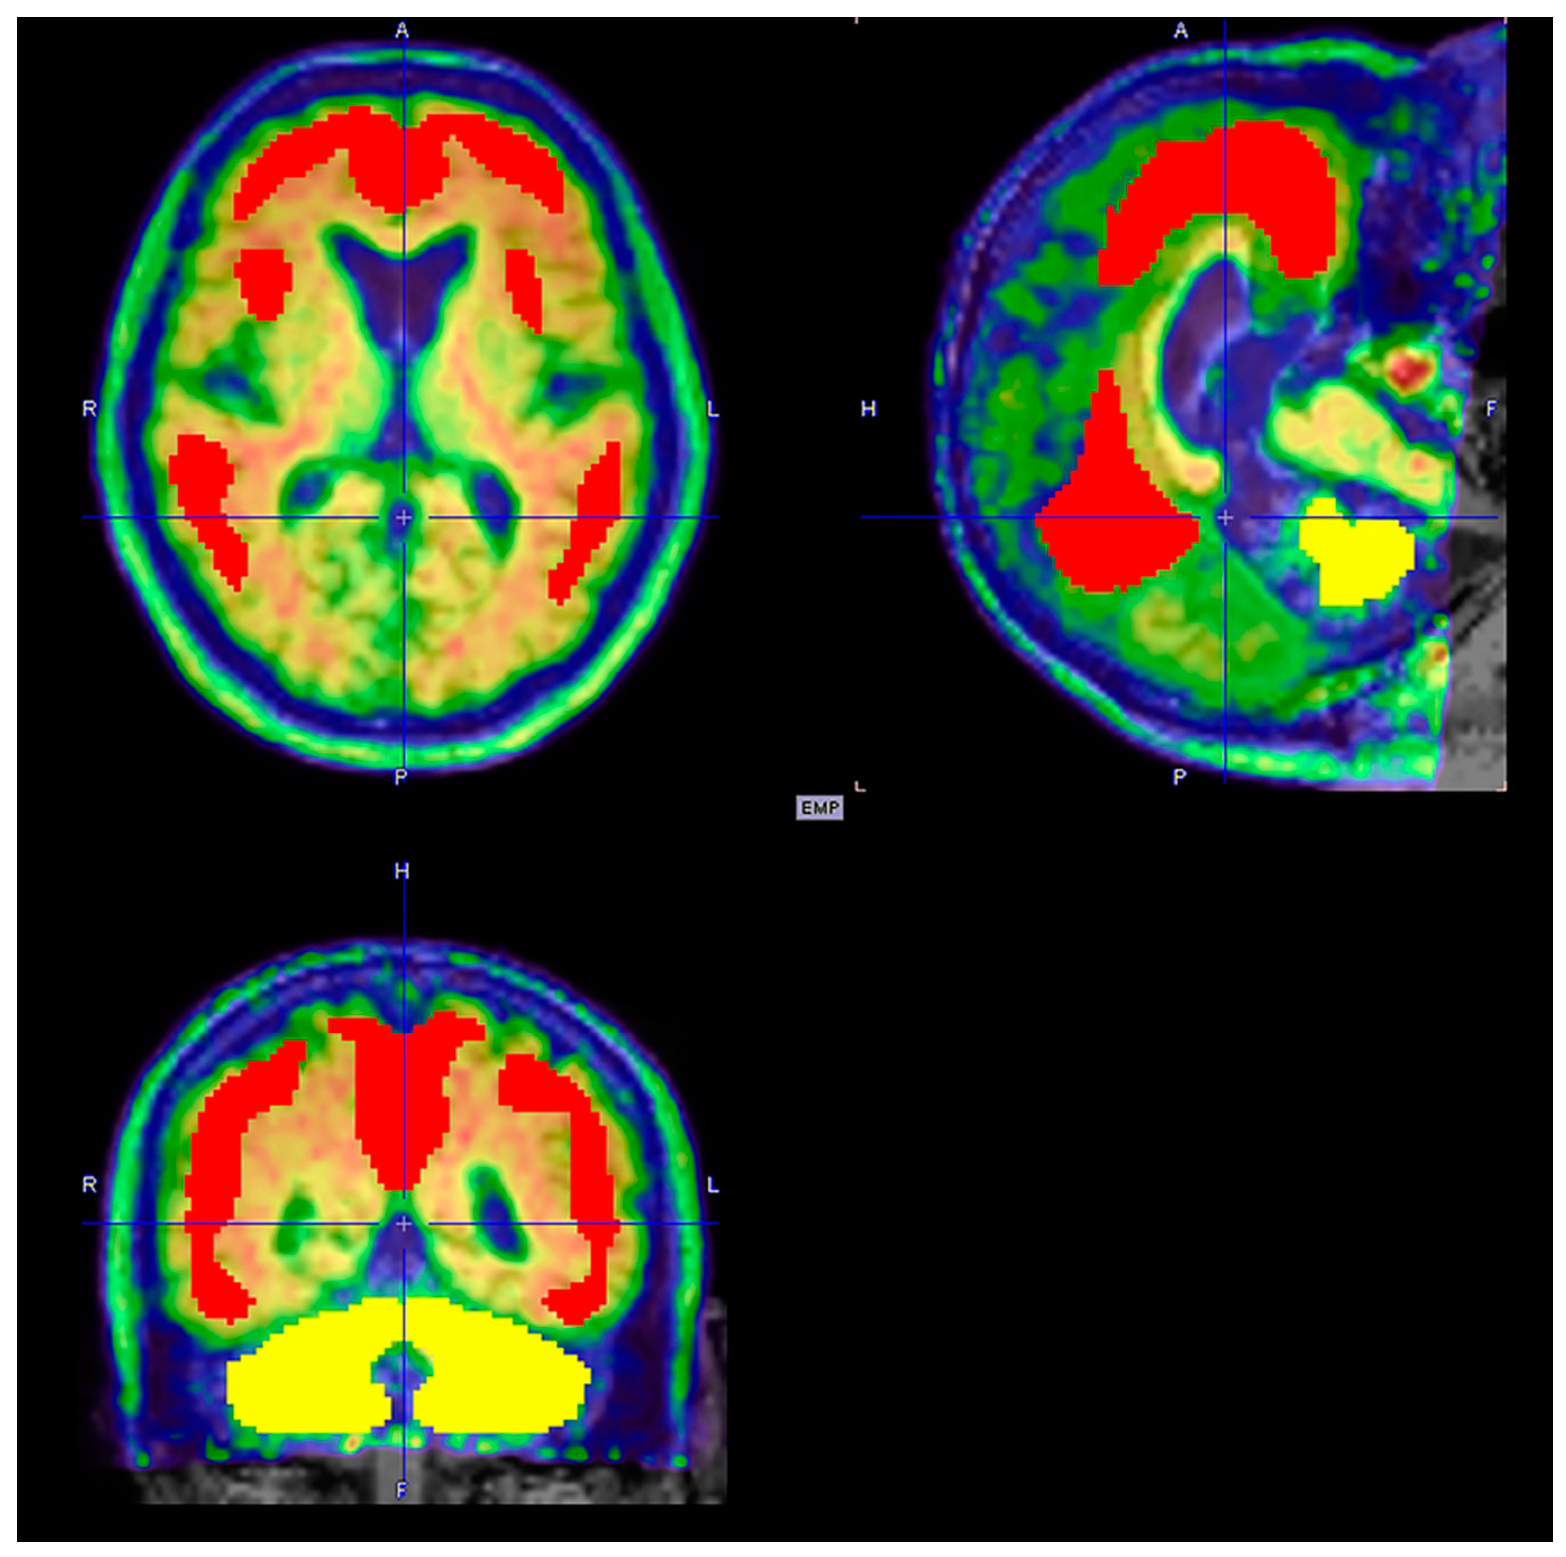

6.1.1. Imaging Data Display [45,50]

| Brain perfusion SPECT |

|

| FDG PET |

| Amyloid and Tau PET imaging |